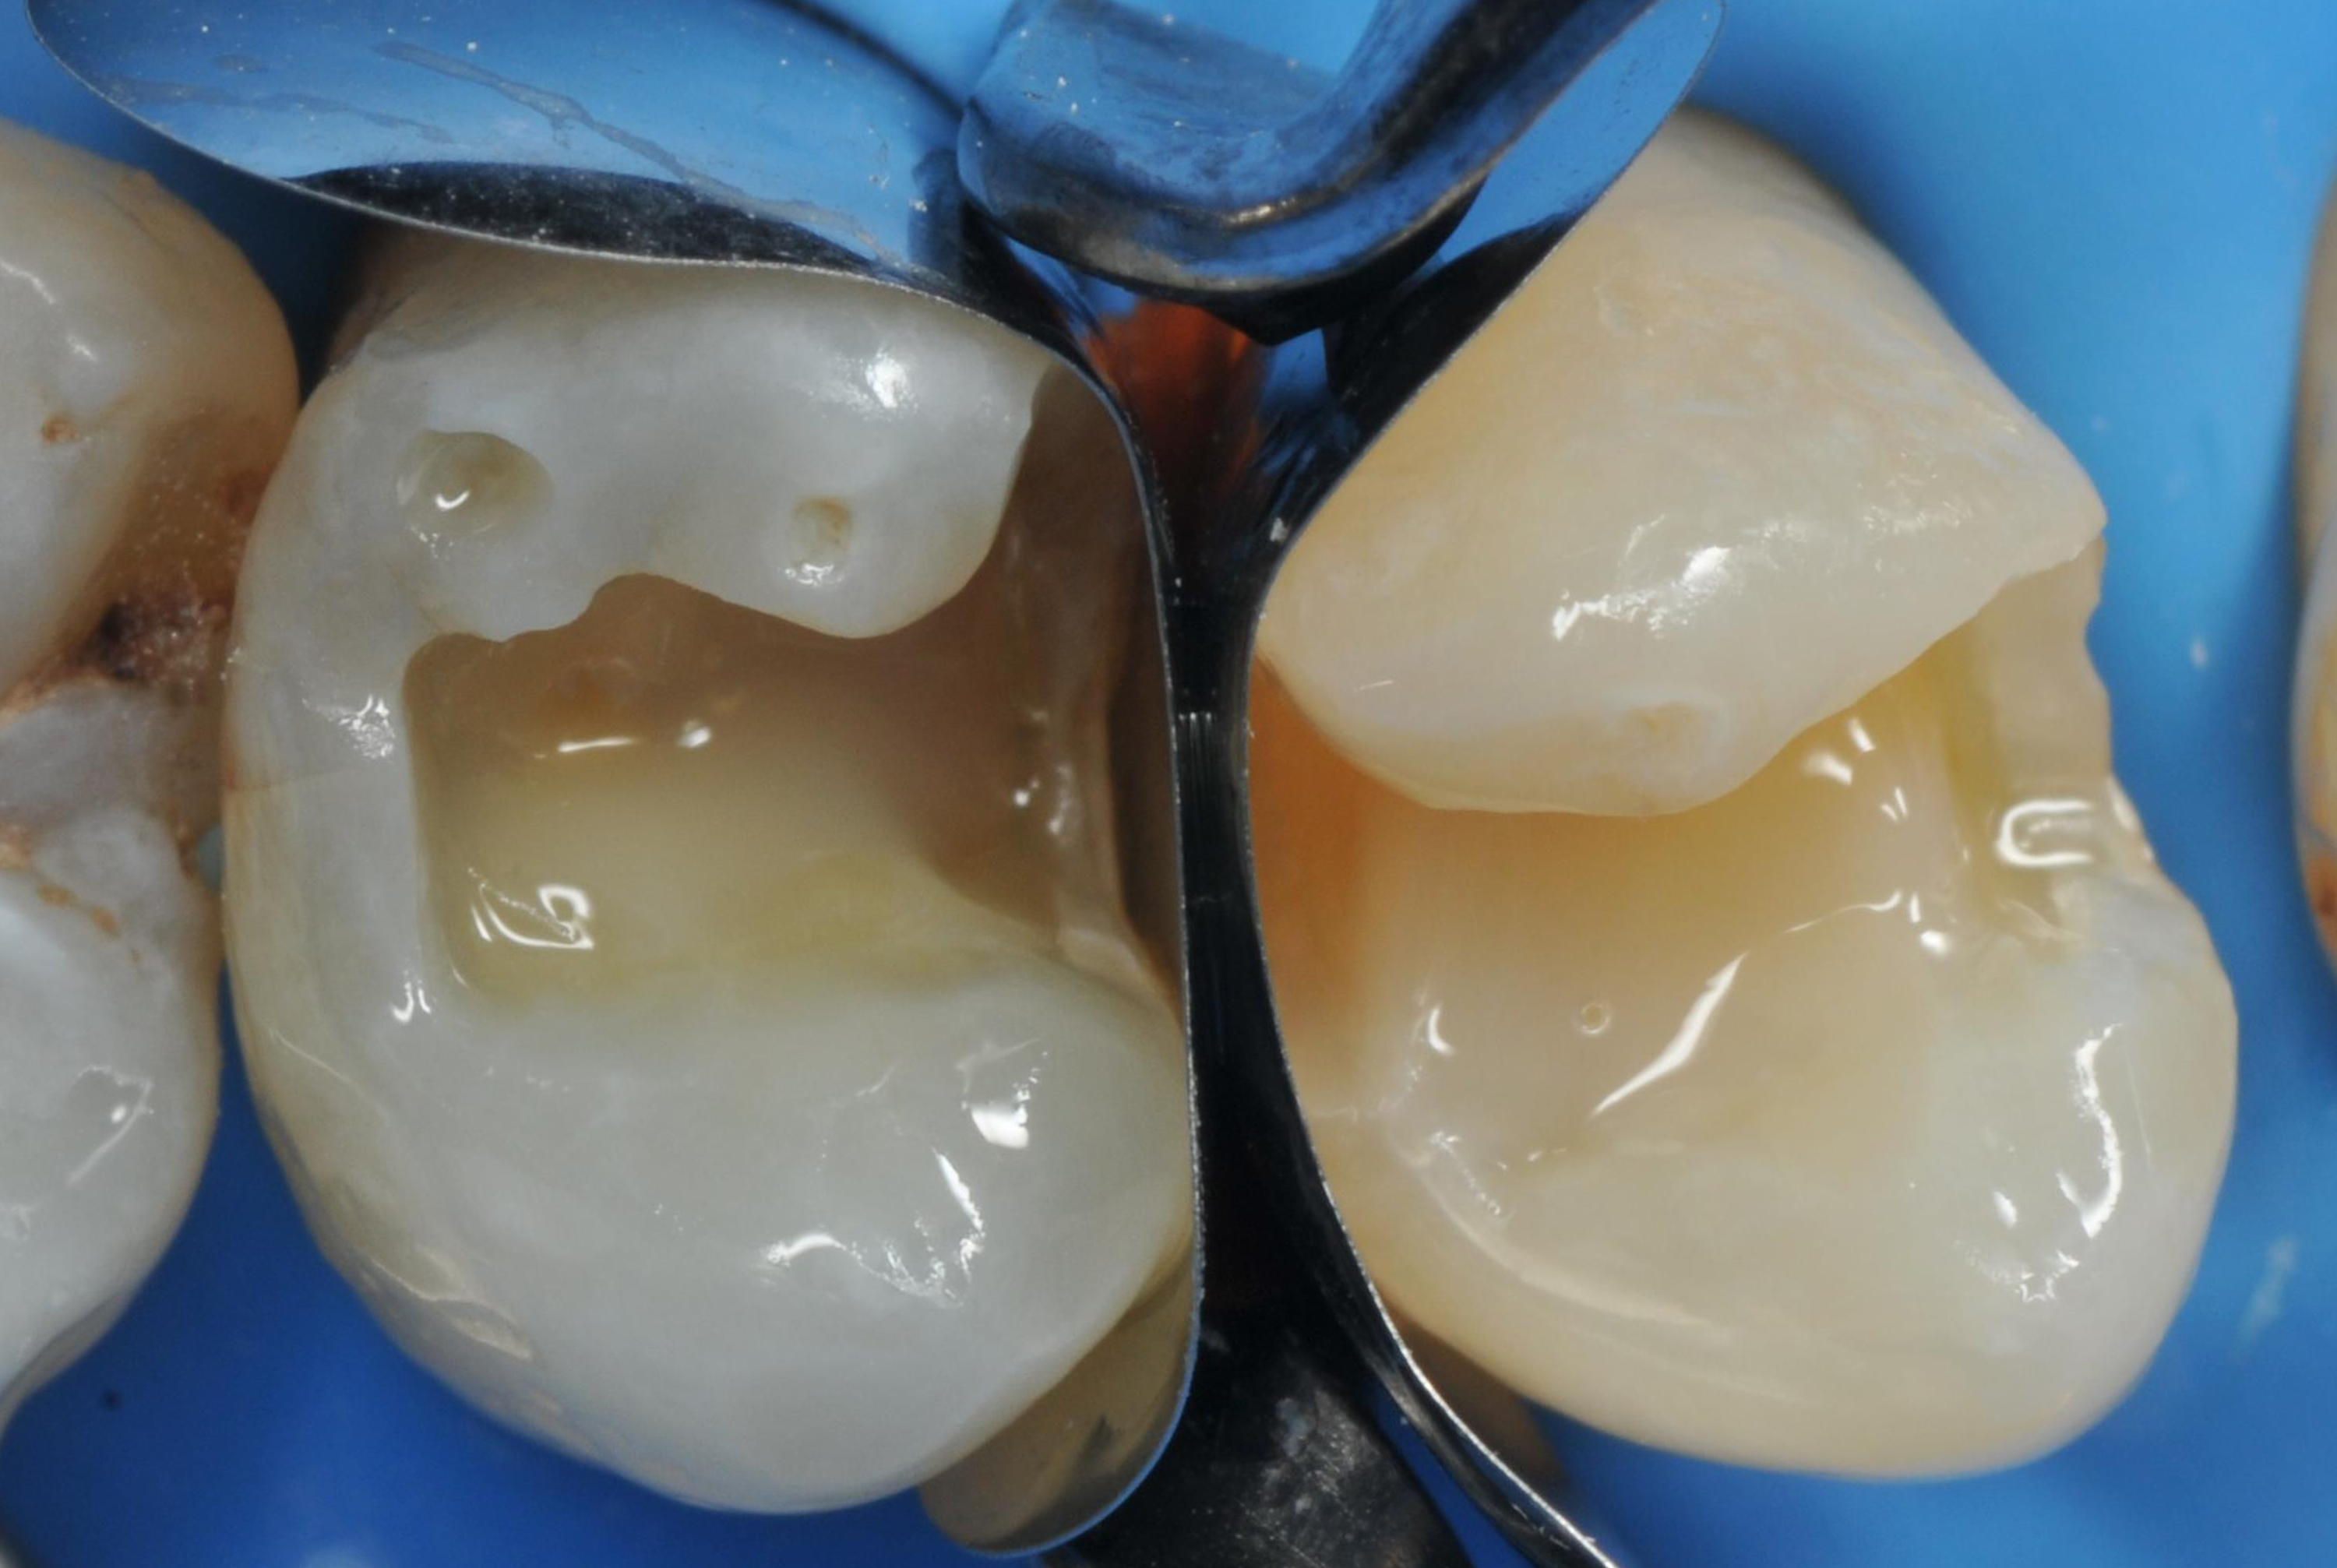

Następnie odłamano zewnętrzną część klina, tak aby w strefie międzyzębowej pozostała tylko jego część (ryc. 4).

W ten sposób pierścień zamknął matrycę tak ciasno, jak to możliwe, na powierzchni zęba, odtwarzając właściwe proporcje obu zębów. Ważne jest, aby prawidłowo uszczelnić matrycę w przestrzeni ubytku klasy II (ryc. 5).